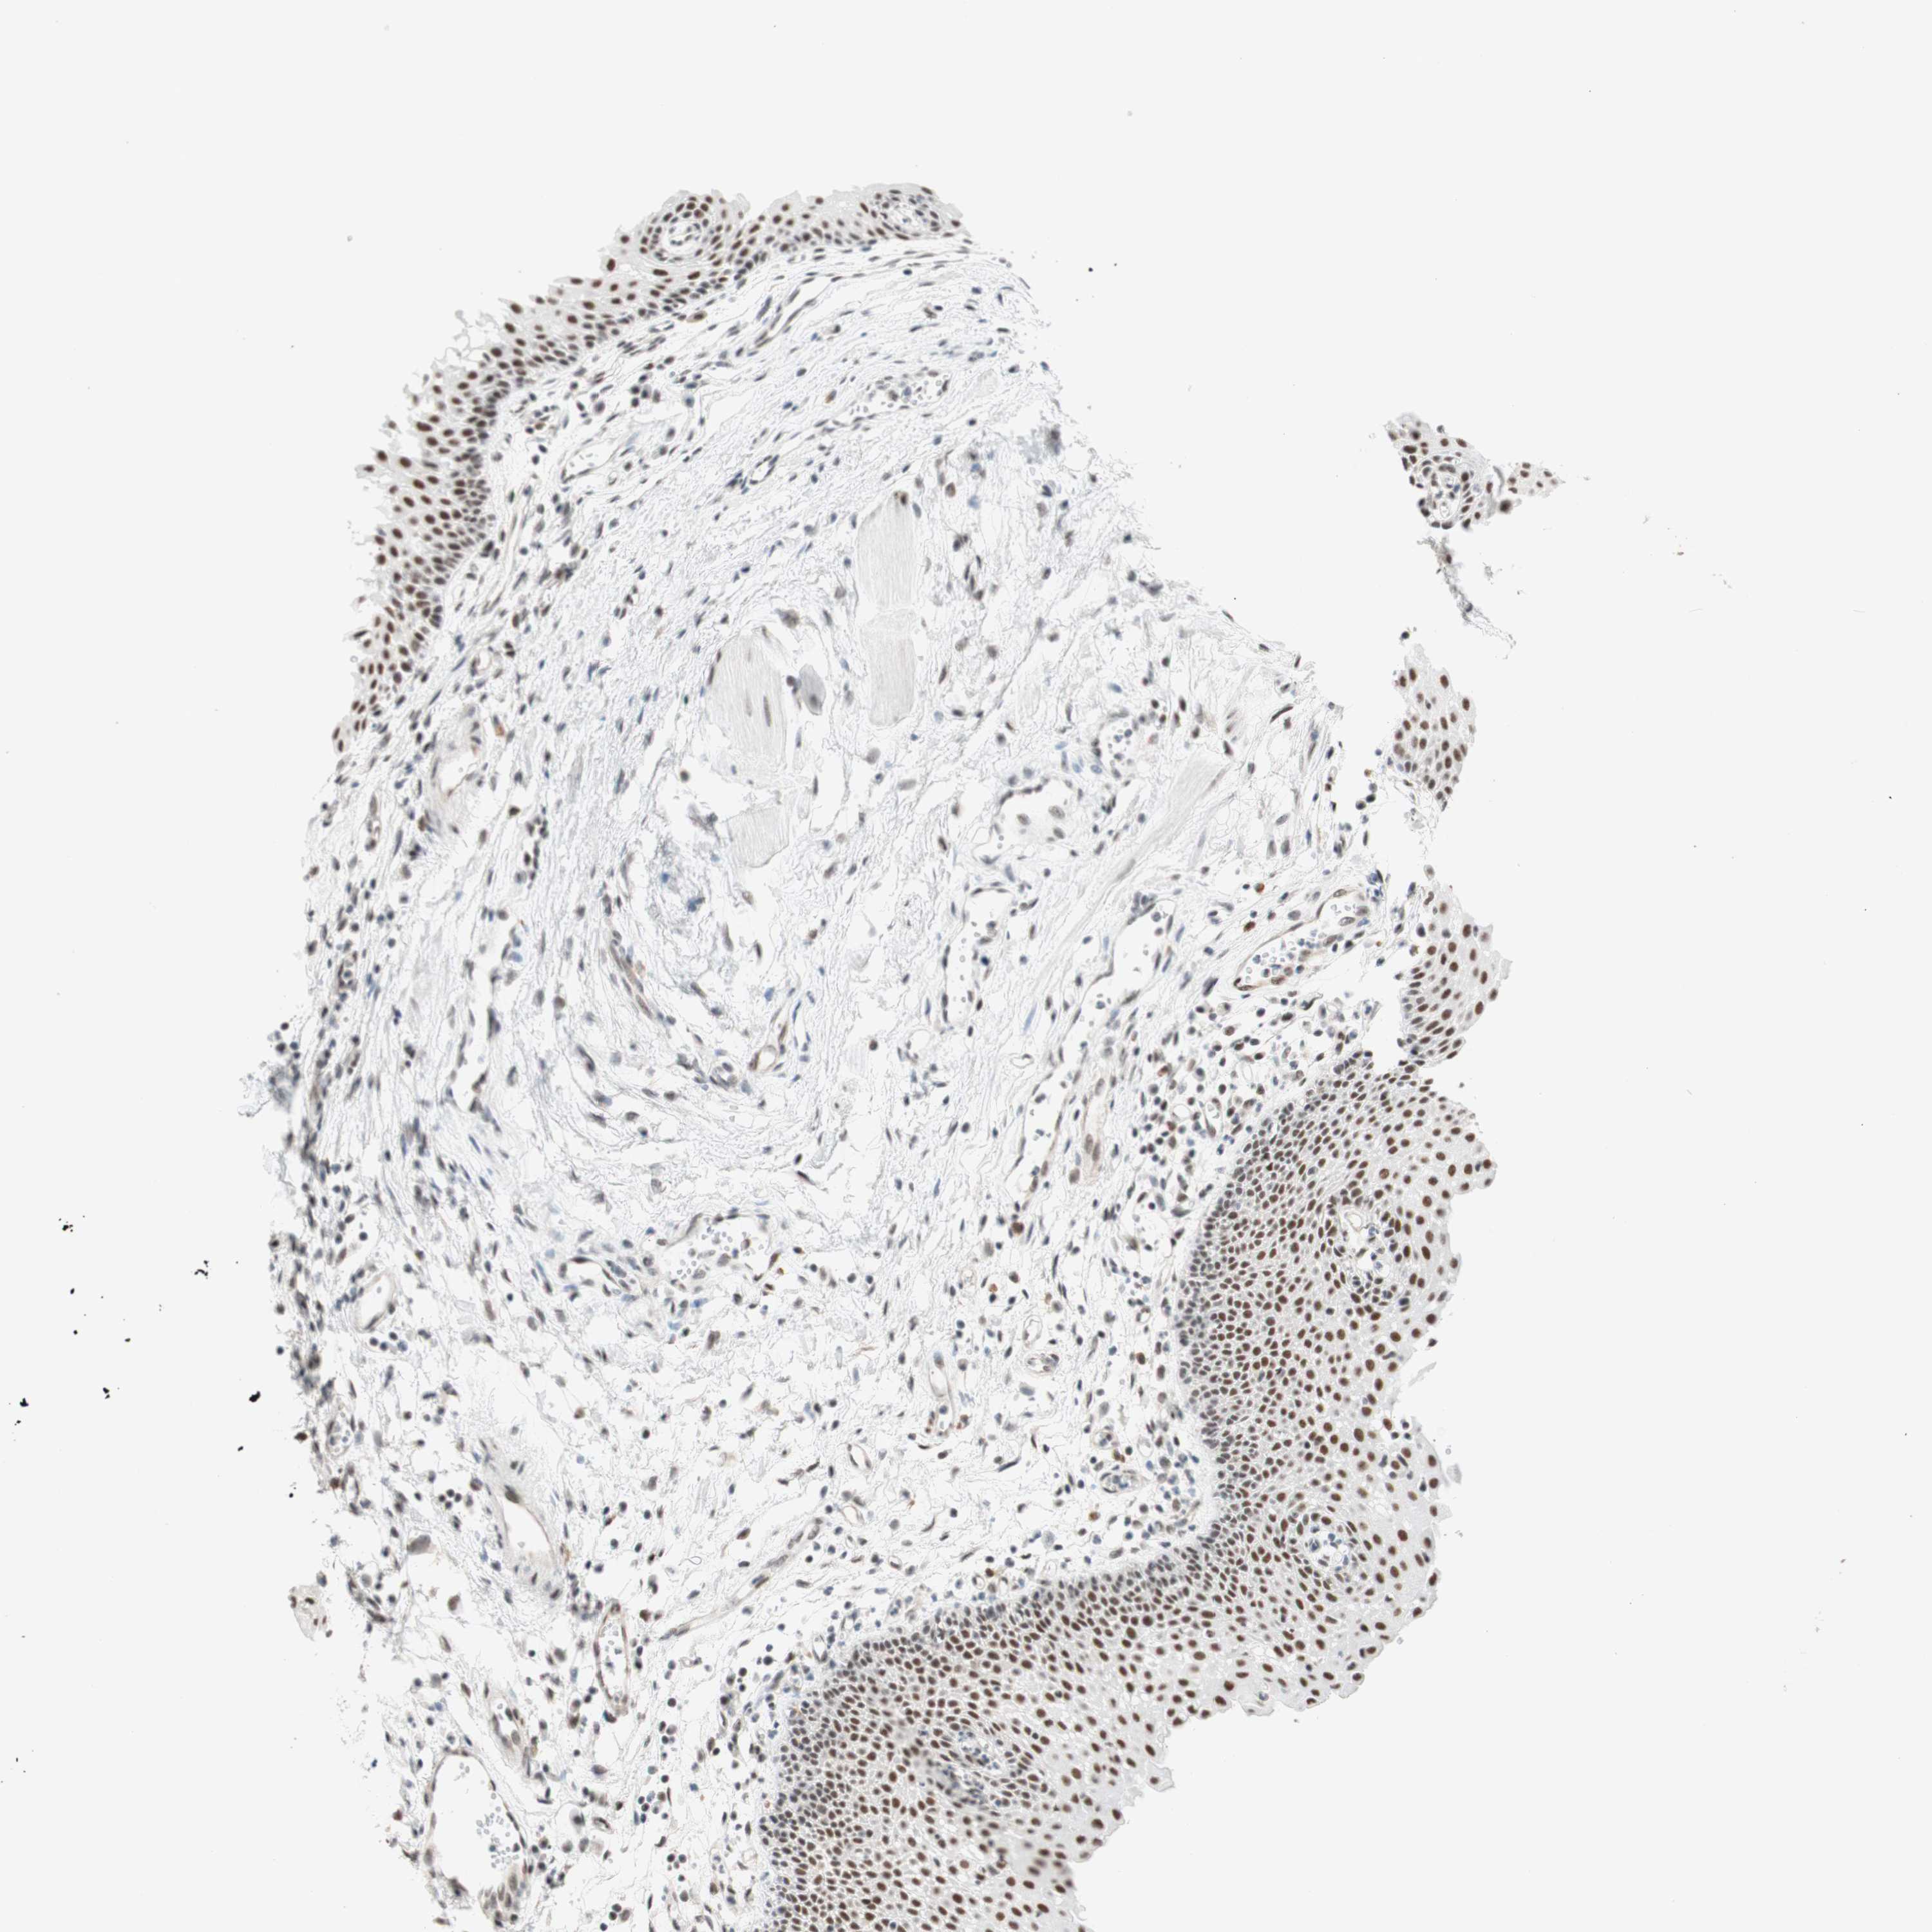

UROTHELIAL CANCER - Protein expressioni

A mouse-over function shows sample information and annotation data. Click on an image to view it in a full screen mode. Samples can be filtered based on level of antibody staining by selecting one or several of the following categories: high, medium, low and not detected. The assay and annotation is described here.

Note that samples used for immunohistochemistry by the Human Protein Atlas do not correspond to samples in the TCGA dataset.

Antibody stainingi

Antibody staining in the annotated cell types in the current human tissue is reported as not detected, low, medium, or high, based on conventional immunohistochemistry profiling in selected tissues. This score is based on the combination of the staining intensity and fraction of stained cells.

Each image is clickable and will lead to virtual microscopy that enables deeper exploration of all samples and also displays staining intensity scores, fraction scores and subcellular localization as well as patient and tissue information for each sample.

Antibody HPA038051

Antibody HPA059070

Antibody CAB012448

Staining

High

Medium

Low

Not detected

Intensity

Strong

Moderate

Weak

Negative

Quantity

>75%

75%-25%

<25%

None

Location

Nuclear

Cytoplasmic/membranous

Cytoplasmic/membranous,nuclear

Urothelial carcinoma, High grade

Urothelial carcinoma, Low grade

Urothelial carcinoma, NOS